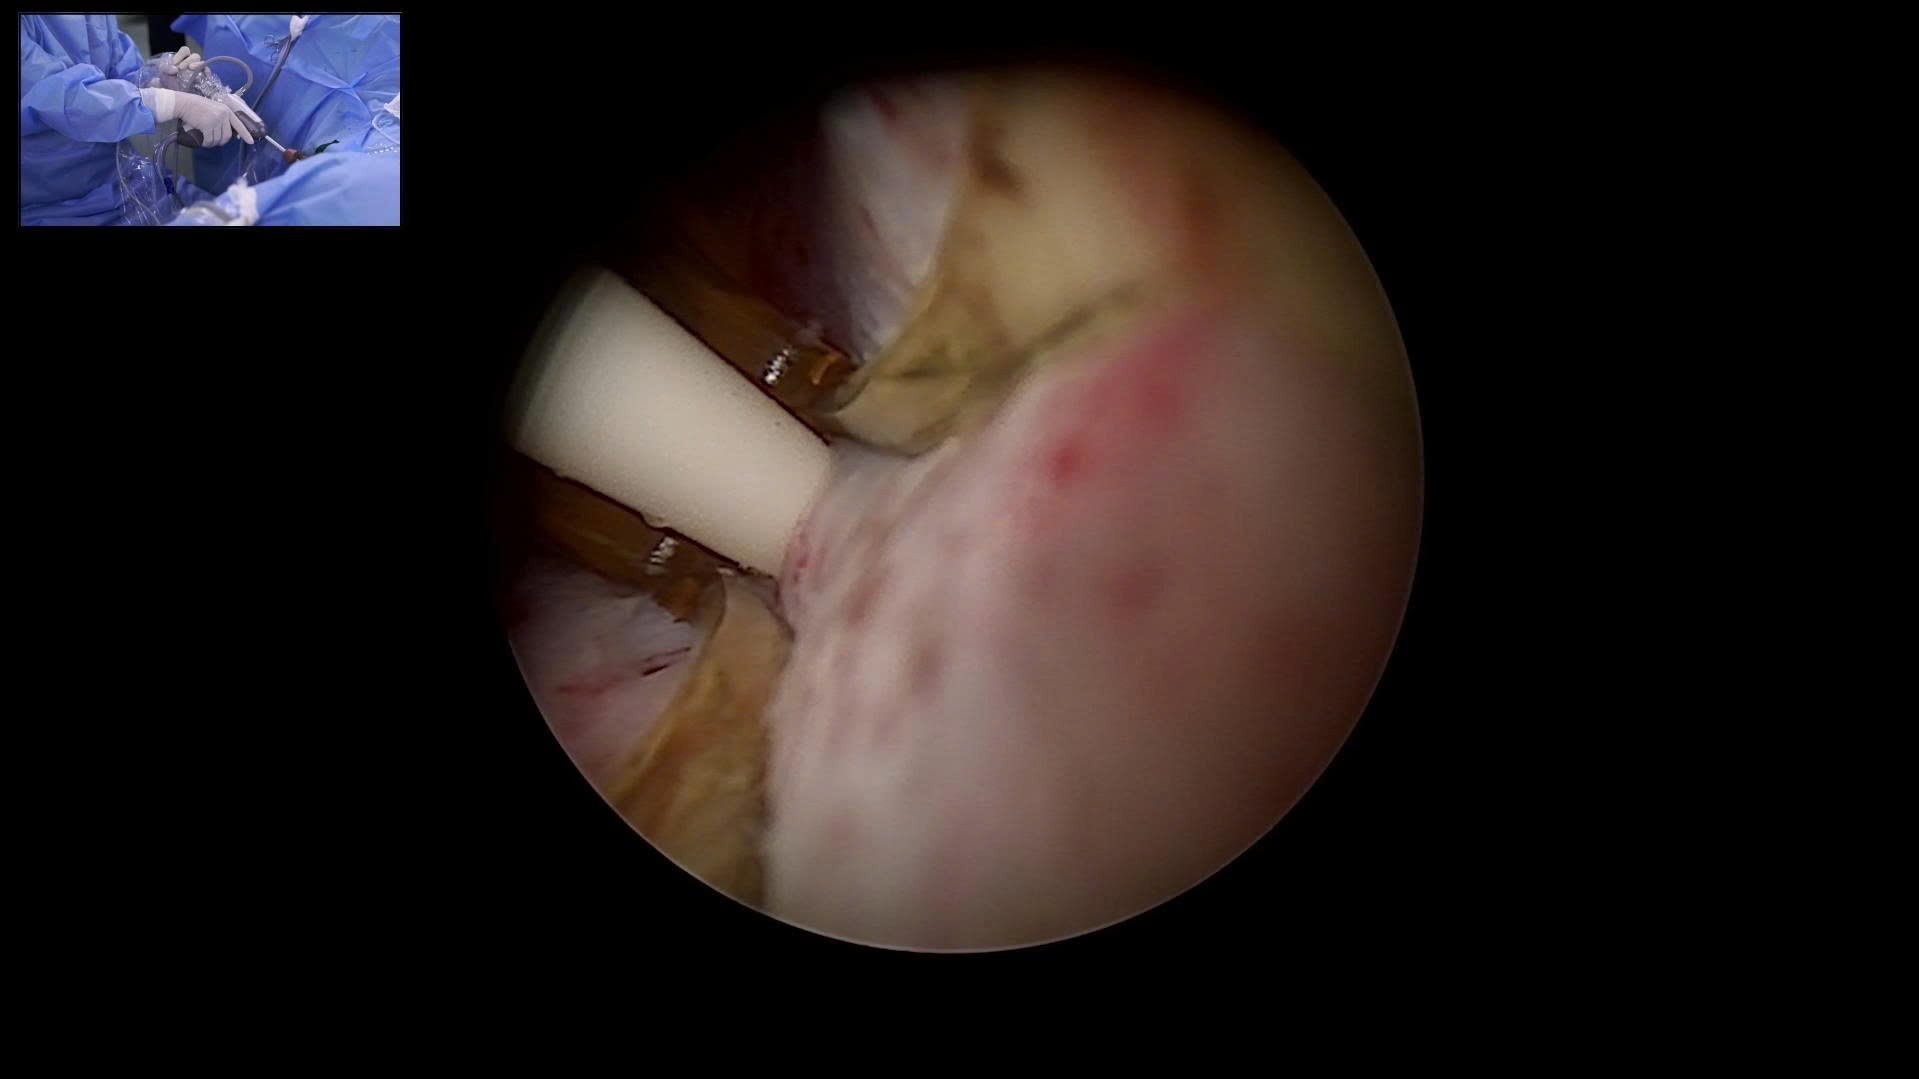

Hình ảnh: Nội soi trong quá trình thực hiện liệu pháp nhiệt hơi nước (Rezūm) tại Bệnh viện Bạch Mai

Hai bệnh nhân đầu tiên được thực hiện liệu pháp Rezūm tại Khoa Phẫu thuật Tiết niệu – Bệnh viện Bạch Mai đã có kết quả rất khả quan: Nước tiểu qua sonde thông ngay sau mổ, không sốt, không đau, không khó chịu. Cả hai đều hài lòng và được xuất viện an toàn chỉ sau một ngày theo dõi. Đặc biệt 02 ca mổ thị phạm được truyền hình trực tiếp với sự tham dự của nhiều giáo sư, chuyên gia đầu ngành trong và ngoài nước, cùng các bác sĩ chuyên khoa tiết niệu từ các bệnh viện tuyến trung ương và tuyến tỉnh đến tham dự, quan sát và học tập kỹ thuật mới. Thành công này, được thực hiện bởi TS.BS. Nguyễn Minh Tuấn, một trong hai bác sĩ Việt Nam đầu tiên được đào tạo bài bản về Rezūm ở nước ngoài, đã khẳng định Bệnh viện Bạch Mai hoàn toàn làm chủ công nghệ.